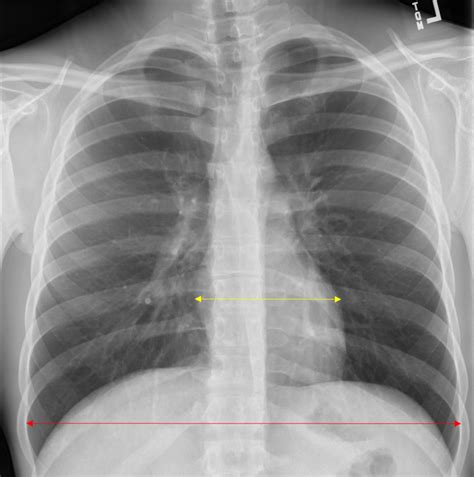

A critical aspect of assessing a chest X-ray is evaluating the cardiothoracic ratio, which is the ratio of the widest diameter of the heart to the widest diameter of the chest (from one inner edge of the rib cage to the other). Normally, this ratio should be less than 0.5. An increased cardiothoracic ratio can indicate cardiomegaly (enlargement of the heart), which might suggest various cardiac conditions. In a normal chest X-ray, the heart size should be appropriate for the patient’s body size, and this ratio can provide a quick and useful indicator of cardiac health.

4. Diaphragmatic Position and Movement

The diaphragm, the major muscle used for breathing, should be at an appropriate level and have a normal contour on a chest X-ray. The position of the diaphragm can be influenced by factors such as lung volume and gravity. In a normal inspiratory chest X-ray, the diaphragm should be at or below the 10th rib anteriorly and the 6th rib posteriorly. Abnormalities in diaphragmatic position or contour can suggest conditions affecting the lungs or the diaphragm itself. Moreover, assessing the movement of the diaphragm during breathing (through fluoroscopy or video X-ray) can provide additional insights into respiratory function.